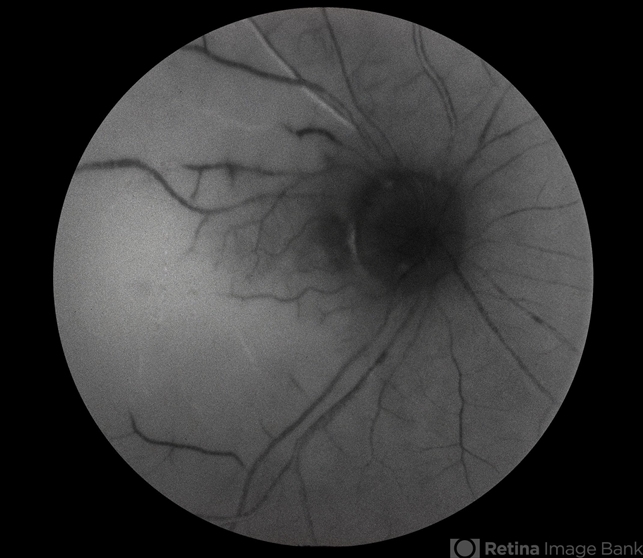

- diabetic mellitus, non-perfusion

- Severe non-perfusion diabetes